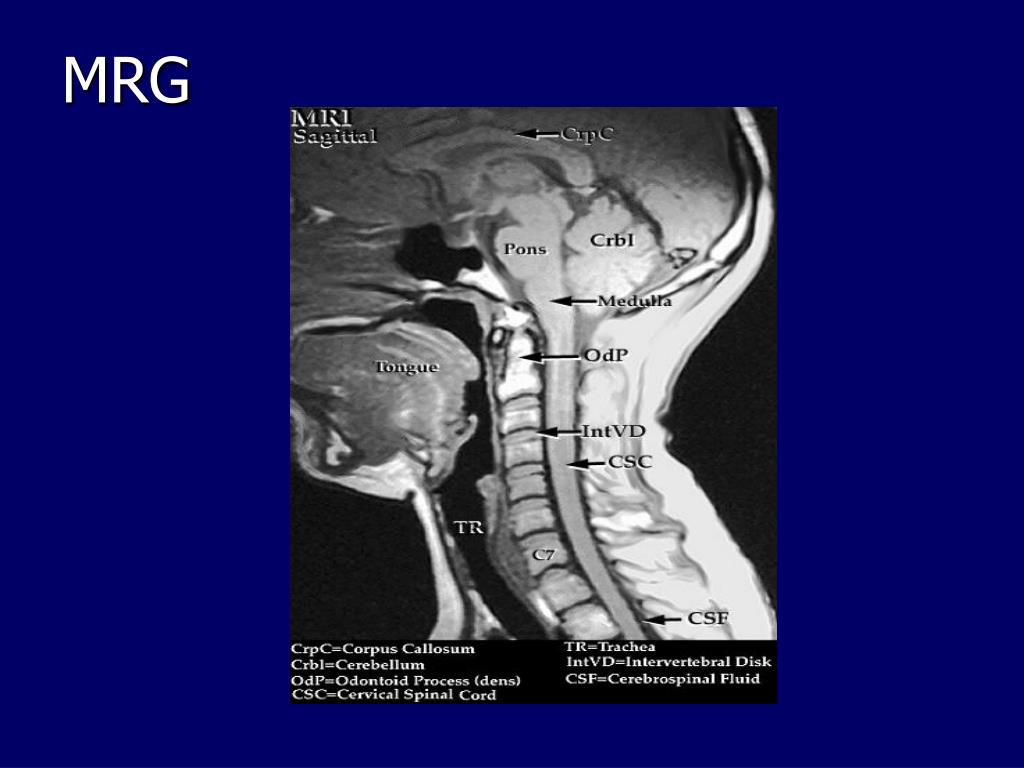

12. Normal Spinal Anatomi: MRG Sagital T2 Görüntü BOS Spinal Kord İntervertebral DisK Anterior Longitudinal Ligament Posterior Longitudinal Ligament ve Dura Mater Dura Mater Ligamentum Flavum